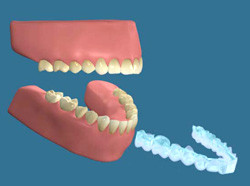

2.マウスピースの作成

それでも強い力で噛みしめる癖のある方は、特に睡眠中にひどく咬み合せによって歯や歯を支えている組織を傷めてしまいます。

そのような方には、睡眠中にナイトガードと呼ばれるマウスピースを装着していただいて、過剰な噛みしめから歯を守ります。